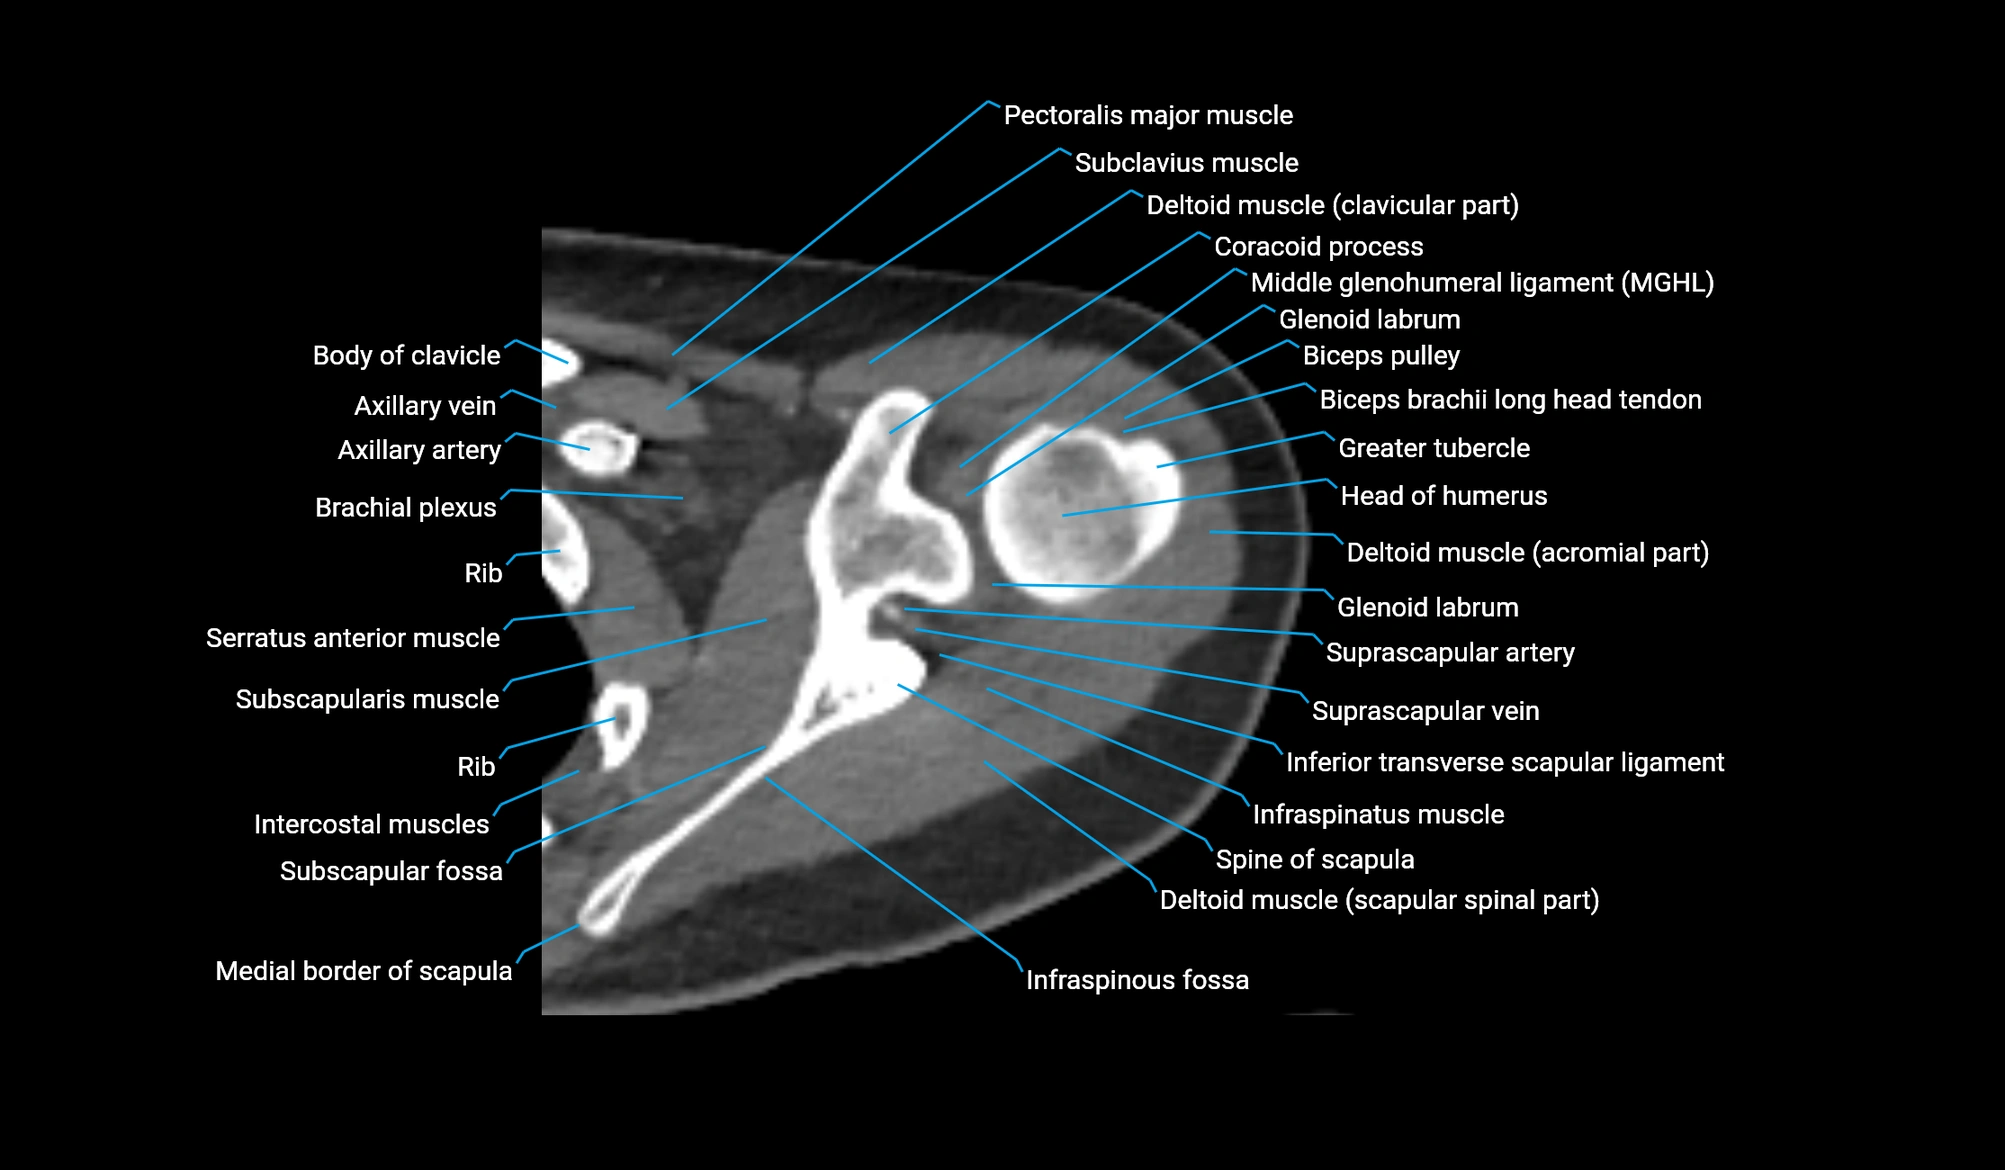

CT image